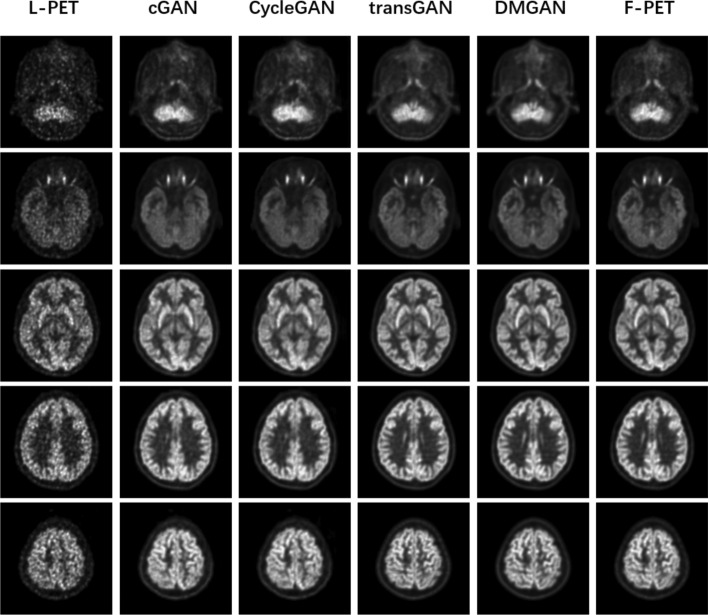

Methods: The proposed method includes two modules: the diffusion generator and the u-net discriminator. The goal of the first module is to get different information from different levels, enhancing the generalization ability of the generator to the image and improving the stability of the training. Generated images are inputted into the u-net discriminator, extracting details from both overall and specific perspectives to enhance the quality of the generated F-PET images. We conducted evaluations encompassing both qualitative assessments and quantitative measures. In terms of quantitative comparisons, we employed two metrics, structure similarity index measure (SSIM) and peak signal-to-noise ratio (PSNR) to evaluate the performance of diverse methods.

Results: Our proposed method achieved the highest PSNR and SSIM scores among the compared methods, which improved PSNR by at least 6.2% compared to the other methods. Compared to other methods, the synthesized full-dose PET image generated by our method exhibits a more accurate voxel-wise metabolic intensity distribution, resulting in a clearer depiction of the epilepsy focus.